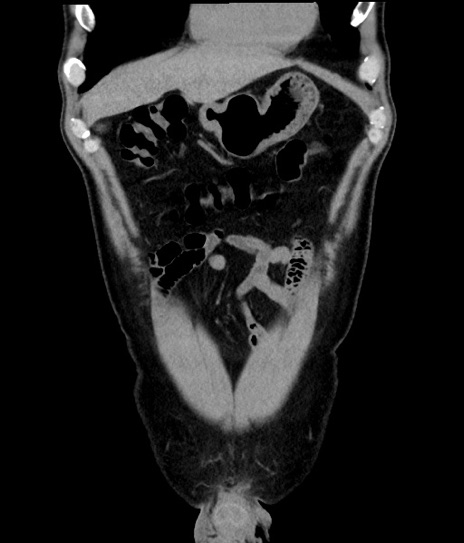

【腹部TIPS】症例44 参考症例① CT(冠状断像)

症例

50歳代男性

横断像